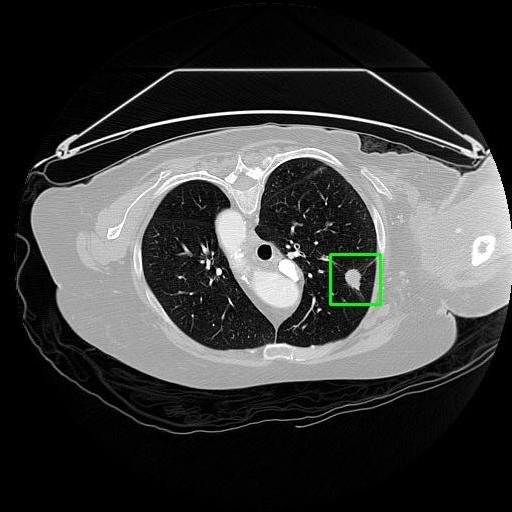

We developed an AI-based system using deep learning models for analyzing lung CT scans to detect and classify pulmonary nodules. We chose the YOLOv11 architecture for its enhanced object detection capability and adapted it specifically for medical imaging, incorporating pixel-level precision and severity classification.

Classification into three severity levels with colored bounding boxes.

Successfully built and deployed an AI model (YOLOv11) capable of detecting lung nodules in CT scans with high accuracy and real-time performance.

Designed a severity classification system that categorizes nodules into null, moderate, and severe using colored bounding boxes, assisting in rapid clinical decision-making.